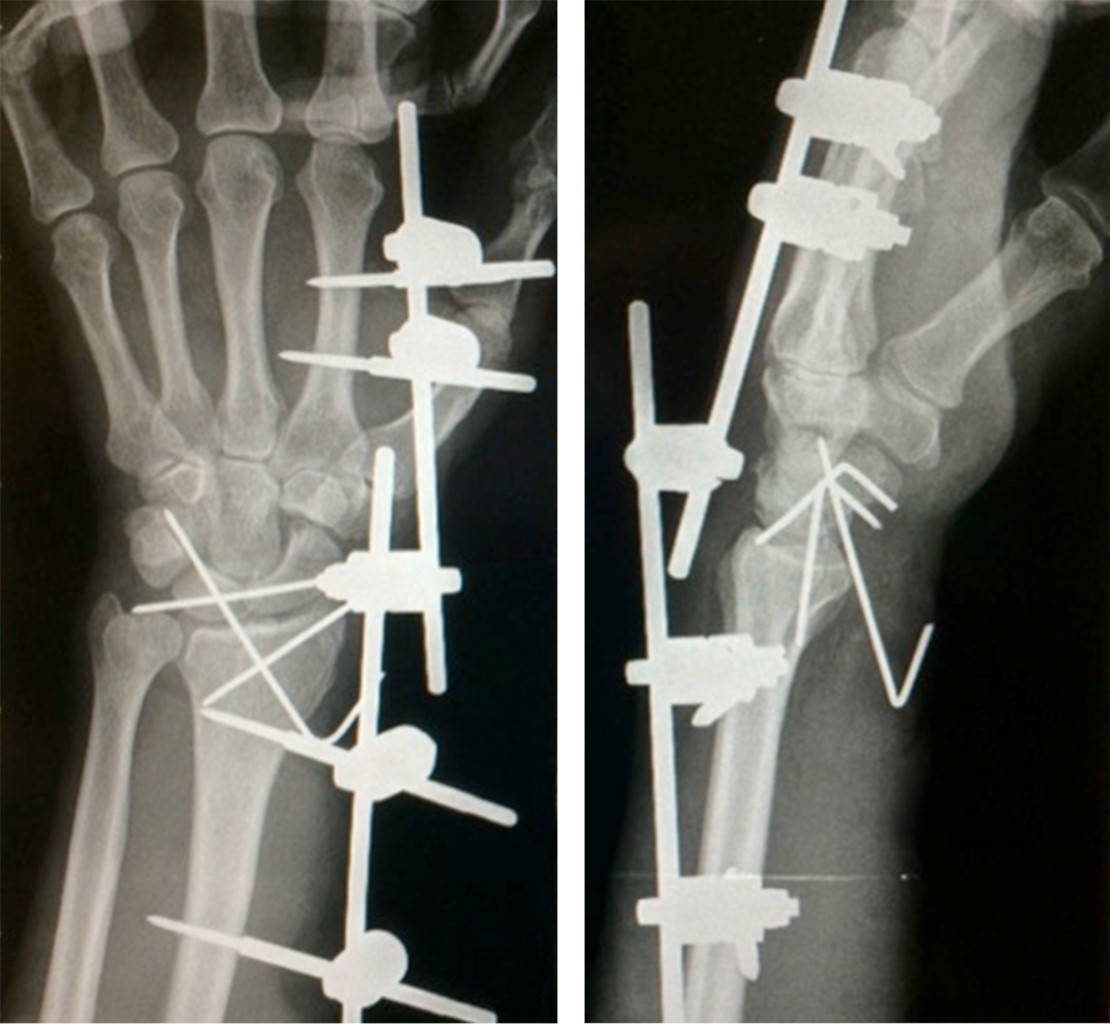

The patient was taken to the OR in which under general anesthesia, three 6.5 mm cannulated screws were used to perform a closed reduction of the lateral condyle of the left femur. In addition, a percutaneous fixation of the left radial styloid and the right radial styloid were performed (Figure 2).

The intention was to bring the bone through the carpal tunnel with the aid of the closed reduction of the lunate. After having proved unsuccessful, a Henry (Volar) approach was made. Later on and with the use of K-wire fixation, the lunate was reduced through the carpal tunnel, thus connecting the scaphoid with the semilunate and then the latter to the capitate.

Stability was verified with an intraoperative X-ray, once ligament reconstruction was performed (Figure 3).

Figure 2

Figure 3